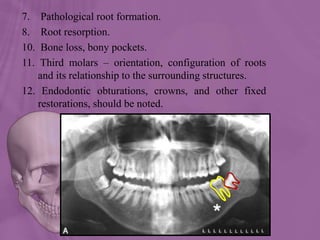

1. Teeth number, position and anatomy should be evaluated.

2. Tooth germ positions.

3. Atypical sequence of eruption.

4. Ectopic tooth germs.

5. Over retained primary teeth.

6. Supernumerary teeth.

7. Pathological root formation.

8. Root resorption.

10. Bone loss, bony pockets.

11. Third molars – orientation, configuration of roots

and its relationship to the surrounding structures.

12. Endodontic obturations, crowns, and other fixed

restorations, should be noted.